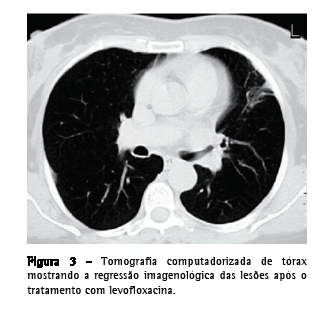

Relato do casoUma paciente do sexo feminino, 55 anos de idade, caucasiana, não fumante, secretária, procurou atendimento no serviço de emergência. Tinha história de hepatite B crônica, hipertensão arterial, dislipidemia mista e múltiplas cáries dentárias não tratadas. Relatou que há três semanas havia iniciado quadro de dejeções diarréicas diárias, azia, desconforto retroesternal agravado pelo decúbito dorsal, astenia, anorexia e emagrecimento (5 kg). Uma semana depois haviam surgido toracalgia esquerda de características pleuríticas com agravamento progressivo, acessos freqüentes de tosse seca ao esforço e pico febril isolado. O eletrocardiograma foi normal, e a endoscopia digestiva alta revelou um cárdia complacente e gastrite antral. A telerradiografia de tórax mostrou hipotransparência heterogênea, esboçando perda de substância em seu seio, no terço médio do campo pulmonar esquerdo. A tomografia computadorizada de tórax evidenciou a presença de uma massa de 4 cm com conteúdo heterogêneo e continuidade pleural ao nível da língula e a presença de dois micronódulos subpleurais na região posterior do campo pulmonar direito (Figura 1). Procedeu-se ao estudo etiológico considerando-se a hipótese diagnóstica de neoplasia pulmonar como a mais provável. Do estudo analítico, salientam-se os seguintes resultados: velocidade de hemossedimentação = 98 mm/1a h; antígeno do câncer 125 = 63,3 U.mL-1 (<35,0); antígeno carcinoembriogênico = 3,55 ng.mL-1 (<2,5) e discreta elevação da proteína C reativa. O estudo imunológico sérico, os marcadores virais e o estudo analítico final não revelaram outras alterações relevantes. Os resultados da colonoscopia, da ultrassonografia abdominopélvica, da mamografia e da citologia cérvico-vaginal foram normais. A primeira fibrobroncoscopia realizada mostrou sinais inflamatórios difusos ao nível da língula. Os resultados do exame citológico de aspirado, lavado brônquico e lavado broncoalveolar foram negativos para células neoplásicas. O exame microbiológico em aerobiose foi também negativo, assim como a pesquisa de bacilos álcool-ácido resistentes. A paciente foi então submetida à biópsia aspirativa transtorácica (BAT), que, ao exame citológico extemporâneo, mostrou um processo inflamatório com supuração. Face a este resultado provisório, iniciou-se a antibioticoterapia com levofloxacina 500 mg via oral ao dia, e decidiu-se realizar uma segunda fibrobroncoscopia. Entretanto, o exame citológico da BAT revelou aspectos morfológicos compatíveis com a presença de Actinomyces, confirmada pelo exame microbiológico cultural do lavado brônquico e broncoalveolar da segunda fibrobroncoscopia, no qual se identificou A. naeslundii (Figura 2). A pesquisa de bacilos álcool-ácido resistentes foi negativa. Dada a melhoria clínica e radiológica após um mês de tratamento (Figura 3), optou-se por manter a antibioticoterapia já iniciada, cuja posologia foi alterada: levofloxacina 500 mg endovenoso ao dia por quatro semanas e, depois, 500 mg po qd. Não se verificou iatrogenia à terapêutica, a qual foi mantida por 16 semanas, até a completa normalização radiológica. Analiticamente constatou-se uma redução da velocidade de hemossedimentação e uma redução de ambos os marcadores tumorais inicialmente alterados, assim como a normalização da proteína C reativa. A paciente foi também submetida a tratamento dentário.